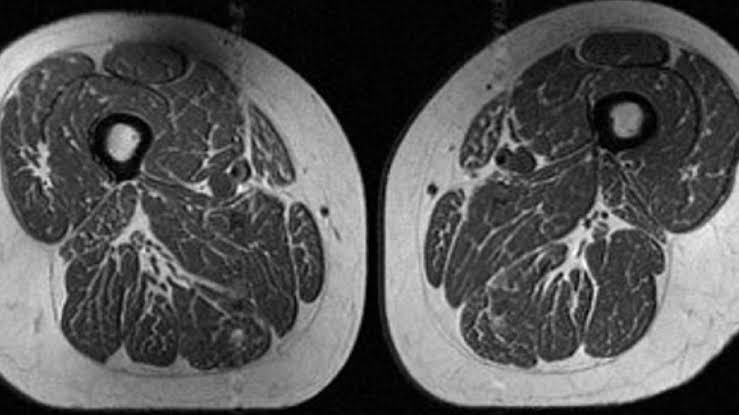

Ultraprocessed foods are turning human thighs into well-marbled steaks